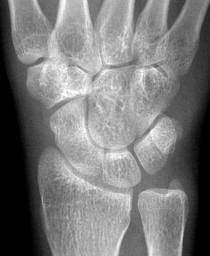

足骨的跖骨(手足短骨解剖及常见疾病的影像学表现)

作者:影像th 概 述 骨是一种器官,主要由骨组织(包括骨细胞、胶原纤 维和基质等)构成外被骨膜,内容骨髓,含有丰富的血管、淋巴管及神经,能不断进行新陈代谢和生长发育,并有修复、 再生和重塑能力骨基质中沉积大量钙盐和...